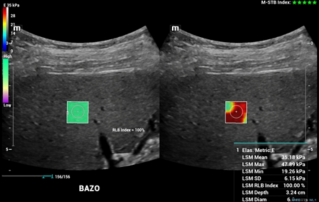

![splenic-stiffness-elastography-esophageal-varices-hepatic-cirrhosis.thumb.319.319 Ultrasound Journal 35 - Correlation between Splenic Stiffness by Elastography and Esophageal Varices in a Patient with Hepatic Cirrhosis: Presentation of a Clinical Case]() Ultrasound Journal 35 - Correlation between Splenic Stiffness by Elastography and Esophageal Varices in a Patient with Hepatic Cirrhosis: Presentation of a Clinical CaseDiscover how shear wave elastography enables early detection of esophageal varices in cirrhosis patients. This clinical case demonstrates how splenic stiffness measurement guides portal hypertension management without invasive procedures.Ultrasound Cases | Ultrasound | Smart applications | Digitalization 2025-04-28

Ultrasound Journal 35 - Correlation between Splenic Stiffness by Elastography and Esophageal Varices in a Patient with Hepatic Cirrhosis: Presentation of a Clinical CaseDiscover how shear wave elastography enables early detection of esophageal varices in cirrhosis patients. This clinical case demonstrates how splenic stiffness measurement guides portal hypertension management without invasive procedures.Ultrasound Cases | Ultrasound | Smart applications | Digitalization 2025-04-28 -